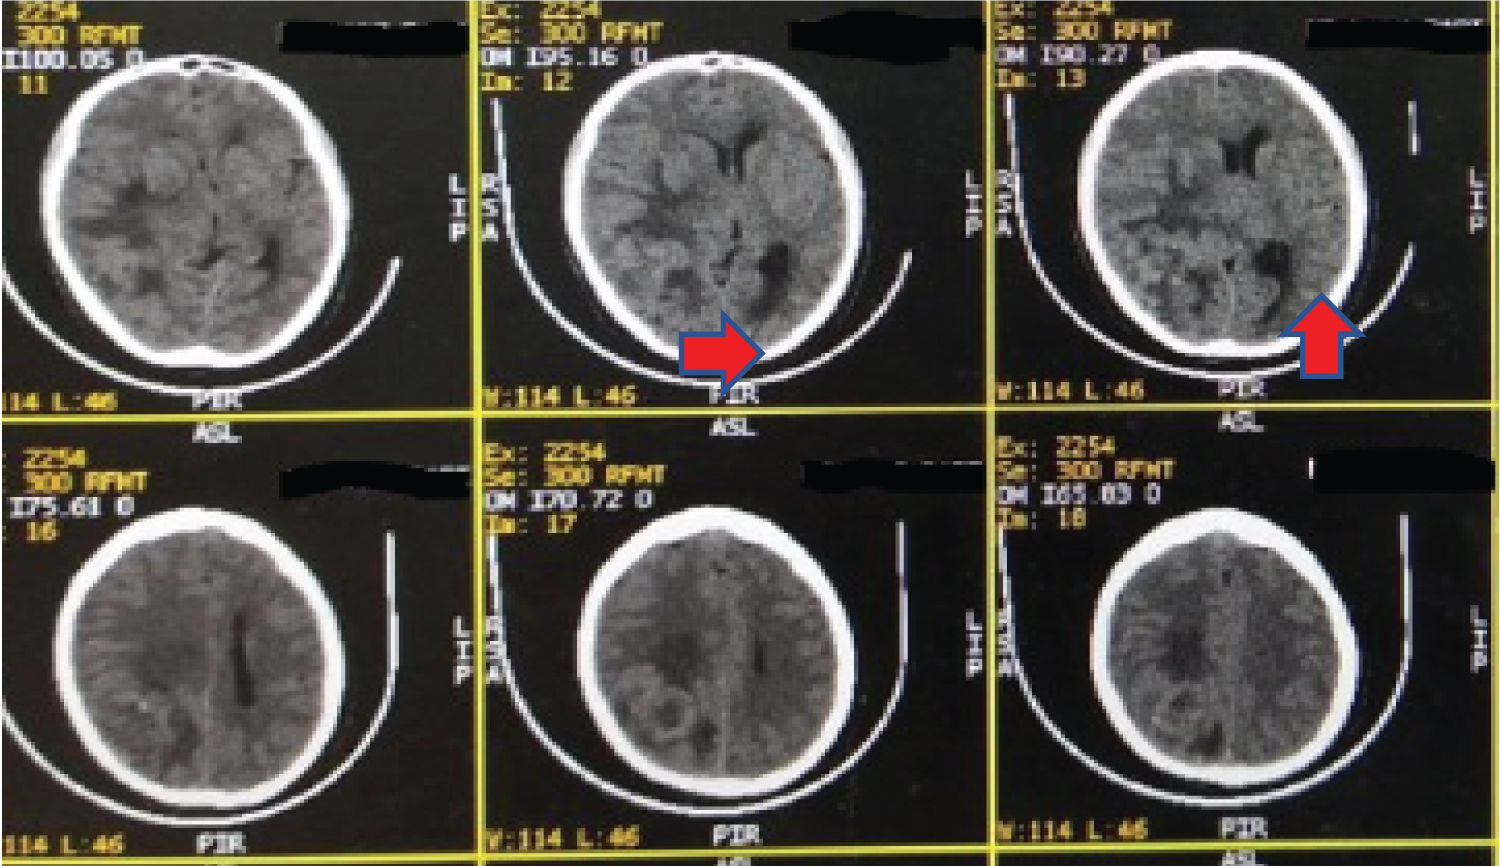

A 63-year-old female presented with progressive headache and visual disturbances in the last two months before admission. She also complained of a limp on the left side in the previous two weeks and was progressive until she couldn't lift her extremities. Vomit is also presented at the time she was admitted to the hospital. General physical examination revealed bilateral visual acuity 1/300, cranial nerve deficits, motor deficits shown as left flaccid hemiparesis, and positive Babinski reflex on the left foot. CT scan with the administration of contrast was done (Figure 1 and Figure 2) and showed a single iso-dense lobulated supratentorial intra-axial solid mass, defined by the irregular border with a distinctive central necrotic and multiple calcified components, measured +/- 5.9 × 4.6 × 4.9 cm, which after contrast administration showed enhancement ring on the right parietooccipital lobe, accompanied by vasogenic edema area, leading to narrowing of the anterior-posterior horn of the right lateral ventricle, third ventricle, and right ambient cisterna, and causing midline shift to the left of +/- 1 cm, suggesting a primary malignant brain tumor, suspected high-grade astrocytoma, calcification of the falx cerebri in the posterior aspect, hypo pneumatization accompanied by left mastoiditis, hypo-pneumatization accompanied by bilateral sphenoid sinusitis. The tumor was resected, and histopathological analysis showed tumor mass with increased cellularity consisting of the proliferation of neoplastic cells forming a diffuse pattern. These neoplastic cells with oval to spindle spherical morphology, mild-moderate pleomorphic nuclei, hyperchromatic, partially with visible nuclei. Mitotic rate showed 14 per 10 high-power fields. Nuclear holes and pseudo-inclusion are visible. The proliferation of blood vessels, tumor cells surrounding the geographic necrosis area, dilation of blood vessels, and bleeding are also visible in this tissue. In another focus, it appears that neoplastic cells are arranged in irregular fasciculus with spindle morphology, narrow eosinophilic cytoplasm, pleomorphic, irregular nuclear membrane, hyperchromatic, partly vesicular chromatin with visible sub-nuclei, and clear cytoplasm (clear cell). The morphology's conclusion follows atypical meningioma (WHO grade II) as shown in Figure 3 and Figure 4.

Figure 1: CT scan without contrast showed a single iso-dense lobulated supratentorial intra-axial solid mass, defined by the irregular border with an irregular central necrotic and multiple calcified components, measured +/- 5.9 × 4.6 × 4.9 cm. View Figure 1

Figure 2: CT scan with contrast showed that enhancement ring on the right parietooccipital lobe, accompanied by vasogenic edema area causing midline shift to the left of +/- 1 cm, suggesting a primary malignant brain tumor, suspected high-grade astrocytoma. View Figure 2

This case showed the CT scan was a single iso-dense lobulated supratentorial intra-axial solid mass, defined by the irregular border with a distinctive central necrotic and multiple calcified components, which on contrast showed enhancement ring contrast, on the right parietooccipital lobe, accompanied by vasogenic edema area, suggesting a primary malignant brain tumor, suspected high-grade astrocytoma. Meningiomas are extra-axial lesions in which CT scan showed intralesional calcification and bony changes. The location of cancer can be seen along the convexity, also generally present as a solitary lesion [7,8]. Imaging atypical meningiomas WHO grade II or meningiomas WHO grade III have a wide range; hence, it is tough to differentiate them solely based on clinical and imaging like the case above. Based on the literature, the imaging of meningiomas WHO grade II and WHO grade III is extra-axial mass with irregular demarcation, intratumorally necrotic areas, extensive brain edema, and changes of the bone. Histopathology analysis is the gold standard to differentiate them well [4,7].